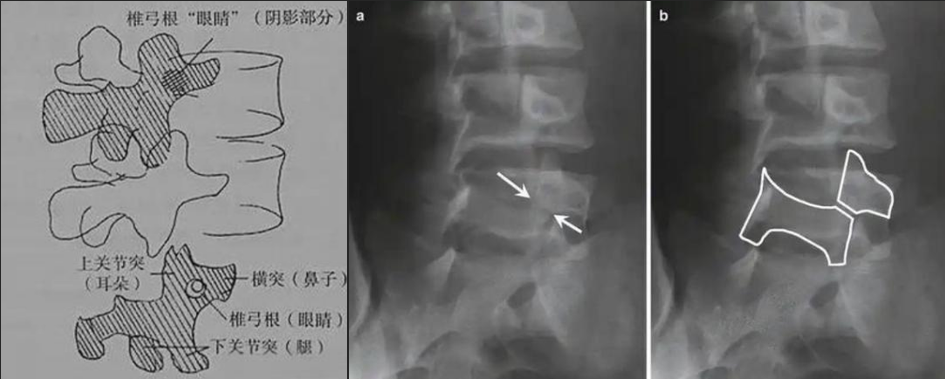

图a和图b 腰椎斜位:狗脖“戴项圈征”,诊断椎体椎弓峡部裂

椎弓根峡部是椎体后部椎弓上最狭窄、最薄弱、但应力最集中的部位,在常规腰椎X线正侧位上,因腰椎其他结构的重叠显示不清,但是在腰椎斜位上,能够清楚完美地展现出来,若其在斜位片上表现为不连续,则可诊断为椎弓根峡部裂,即腰椎的关键承重部分的骨质断裂,这是导致青少年和运动员腰痛的主要原因。

在腰椎斜位片上,腰椎的附件结构形成了一个经典的“斯科蒂狗”图案,其中“狗脖子”处即代表椎弓根峡部,若“狗脖子”上出现了一条透亮清晰的线,就像给狗戴了一条“项链”,即“戴项圈征”,这是诊断椎弓峡部裂的直接证据。